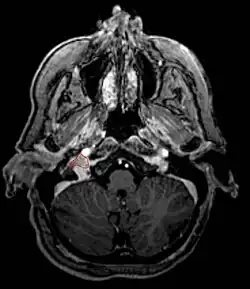

- Commonly arise from the paraganglia of the jugular bulb

- Typically invade the tympanic cavity and jugular foramen

- Can extensively invade petroclival region

- Can invade cavernous sinus above

- Can invade hypoglossal canal below